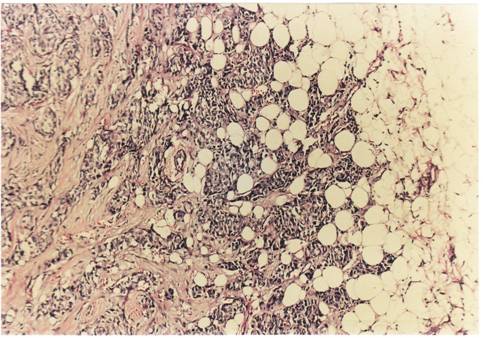

Criterii microscopice de diagnosticare a cancerului mamar

Pentru examenul histopatologic piesele de mamectomie sunt prelucrate prin imparafinare si colorate cu Hematoxilina-Eozina sau, pentru observarea mai buna a tesutului conjunctiv, cu Van Gieson.

Pe preparate colorate, la microscopul optic se observa urmatoarele imagini :